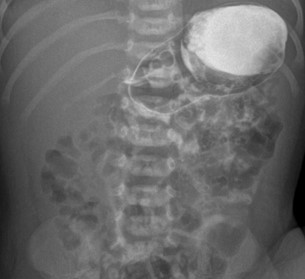

Рисунок 4 - Ребенок возрастом 2 месяца 10 дней, пассаж контрастного препарата

Примечание: рентгенограмма, полученная через час после введения контраста, положение лежа на спине, контрастный препарат поступил в тонкую кишку, визуализируется двенадцатиперстная кишка, дуоденоеюнальный переход расположен левее левой ножки позвонка, ниже пилоруса (норма)